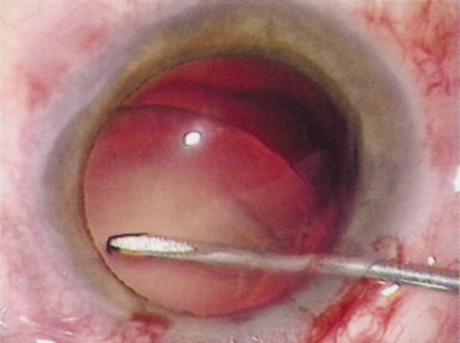

Many patients are most bothered by cataract-induced glare. For these patients, acuity testing under glare situations is indicated. There are several methods to assess visual acuity reduction by glare. The choice of method is often best dictated by the patient's history. If a patient complains of glare problems in the supermarket, or other uniformly illuminated environment, the brightness acuity test can be performed (Mentor Ophthalmics). For this test, the specially illuminated handpiece is held in front of the tested eye using best spectacle correction (Fig. 1). The Snellen acuity is rechecked and can be recorded on each of three light settings.